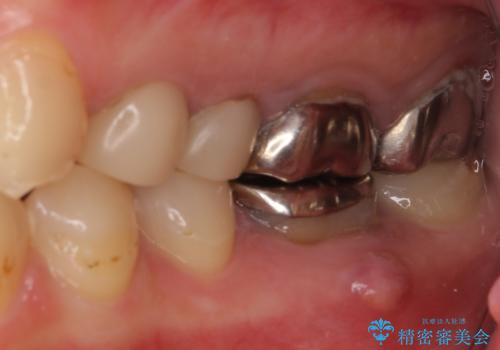

結婚式前に目立つ銀歯をセラミックに

- 笑ったときに見てしまう上顎奥歯の銀歯を気にして来院された患者様です。

折角セラミッククラウンを装着するので、根管治療を行った後に補綴治療を行うこととしました。

他にも目立つ銀歯がありましたが、最も気にしている2本を優先して行うこととしました。